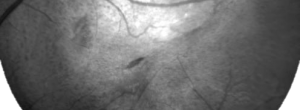

Optical Coherence Tomography Assessment of Apparent Foveal Swelling in Patients with Foveal Sparing Secondary to Geographic Atrophy.

GAIN. Characterization of geographic atrophy progression in patients with age-related macular degeneration: evolution and risk factors associated with geographic atrophy progression

GAP. A phase I escalating dose of subretinal sodium iodate: a toxi-induced animal model of geography atrophy of RPE and phtotoreceptors